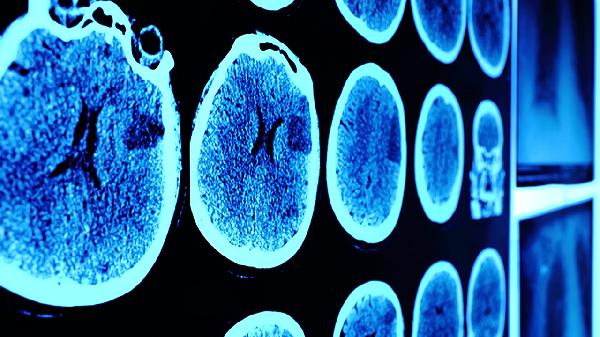

脑震荡属于轻度创伤性脑损伤,其症状通常在头部受到外力冲击后即刻或短时间内出现。部分患者可能在受伤后数分钟至数小时内才感到头晕、恶心等症状,这与脑组织瞬间位移引起的神经功能暂时性紊乱有关。典型表现包括短暂意识丧失、头痛、思维混乱、对受伤过程记忆模糊等,这些症状往往在24小时内达到高峰。影像学检查如CT或MRI通常无结构性损伤,诊断主要依赖临床症状和受伤史。